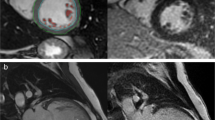

CMR-based volumetric assessments included left atrial (LA) and left ventricular (LV) end-diastolic volumes (EDV) as well as end-systolic volumes (ESV) using dedicated post-processing software (Qmass, Medis Medical Imaging Systems, Leiden, The Netherlands). Left atrioventricular coupling index (LACI) was calculated as ratio between LA EDV and LV EDV and expressed as a percentage [24]. LA and LV volumes were measured in the same end-diastolic phase. Strain values were analyzed using established and validated Feature-Tracking FT software (TomTec Imaging Systems, Unterschleissheim, Germany) as previously described and an average from three measurements was calculated [8, 25] (Fig. 1).

LA long axis strain (LAS) was analyzed as previously described [26]: Initially, a line connecting the origins of the mitral leaflets was set. Subsequently, a line connecting to the LA posterior portion of the greatest distance in regard to the reference line was plotted (Fig. 2). CMR-FT-derived LA strain values were divided into three functional components: 1) total strain (Es) corresponding to atrial reservoir function describing the collection of venous return during ventricular systole, 2) passive strain (Ee) corresponding to atrial conduit function representing blood flow to the ventricle during early ventricular diastole and 3) active strain (Ea) reflecting atrial booster pump function as an amplification of ventricular filling during late diastole (Fig. 3 A)[27].

Illustration of left atrial long axis strain (LA LAS) in long-axis 2- and 4- chamber view (CV) at left ventricular end-diastole (ED) and end-systole (ES). LA LAS was analyzed as previously described [26] assessed between the middle of a line connecting the origins of the mitral leaflets and a line linking the LA posterior portion of the greatest distance in regard to the middle of the mitral reference line